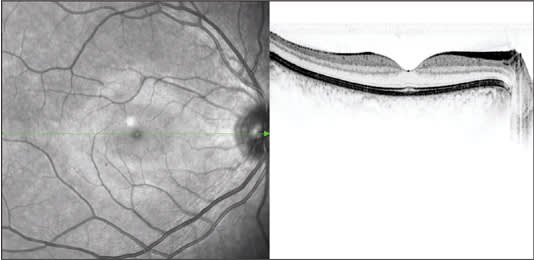

"Three-D volume scans are helpful for identifying pathology in suspicious areas," he continues. "Volume scans are a series or stack of parallel B-scans, which are aligned to one of the instrument's reference fundus images, such as infrared or autofluorescence. If a suspicious area is seen, I can literally page through the B-scans to look for any signs of pathology. (Figures 1 and 2)

Figure 1. This reflectance image from the Spectralis is an example of simultaneous imaging.

PHOTOS COURTESY OF HEIDELBERG ENGINEERING